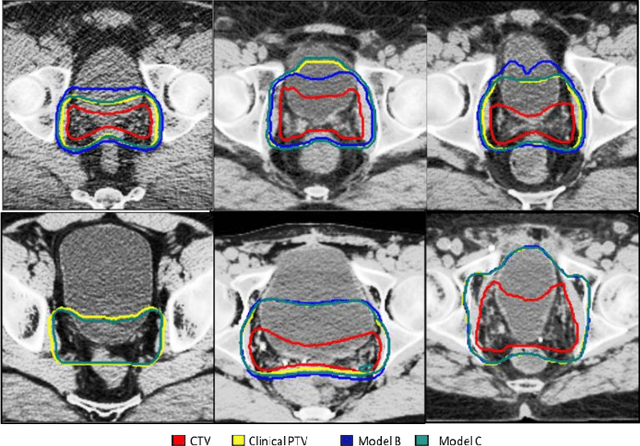

Abstract:When a pre-trained general auto-segmentation model is deployed at a new institution, a support framework in the proposed Prior-guided DDL network will learn the systematic difference between the model predictions and the final contours revised and approved by clinicians for an initial group of patients. The learned style feature differences are concatenated with the new patients (query) features and then decoded to get the style-adapted segmentations. The model is independent of practice styles and anatomical structures. It meta-learns with simulated style differences and does not need to be exposed to any real clinical stylized structures during training. Once trained on the simulated data, it can be deployed for clinical use to adapt to new practice styles and new anatomical structures without further training. To show the proof of concept, we tested the Prior-guided DDL network on six different practice style variations for three different anatomical structures. Pre-trained segmentation models were adapted from post-operative clinical target volume (CTV) segmentation to segment CTVstyle1, CTVstyle2, and CTVstyle3, from parotid gland segmentation to segment Parotidsuperficial, and from rectum segmentation to segment Rectumsuperior and Rectumposterior. The mode performance was quantified with Dice Similarity Coefficient (DSC). With adaptation based on only the first three patients, the average DSCs were improved from 78.6, 71.9, 63.0, 52.2, 46.3 and 69.6 to 84.4, 77.8, 73.0, 77.8, 70.5, 68.1, for CTVstyle1, CTVstyle2, and CTVstyle3, Parotidsuperficial, Rectumsuperior, and Rectumposterior, respectively, showing the great potential of the Priorguided DDL network for a fast and effortless adaptation to new practice styles